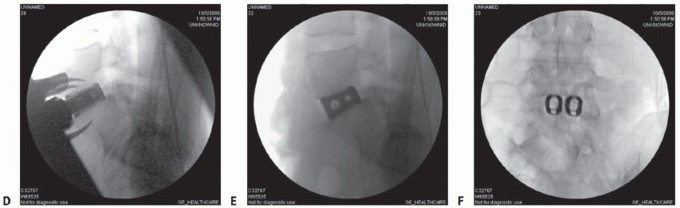

- TECH FIG 4 • AP (A) and lateral (B) fluoroscopic images showing midline positioning and screw trajectories of stand-alone ALIF device.

Typically, a single interbody cage that spans the disc space is selected, with graft material packed on both sides within the implant. This is positioned in the center of the interspace using product-specific instruments (TECH FIG 4A).

Locking screws are directed cephalad and caudad either through the cage device or through a metal faceplate that attaches to the cage (TECH FIG 4B). Knowledge of productspecific screw trajectories and starting points is paramount as they may be either symmetric about the midline or translated left or right to allow safe passage of the drill between the iliac vessels. - Adjunct Treatments

Under fluoroscopic guidance, determine the midline on a true AP image of the vertebral body above or

below the disc (TECH FIG 5A). A bone screw may be inserted as a reference.

Sizing guides are trialed to fill the entire footprint of the endplate (TECH FIG 5B). Height and lordosis are then set using trial wedges (TECH FIG 5C-E) and should match the resected gap and preoperative templating.

- TECH FIG 5 • A. True AP fluoroscopic image. The distance between the midpoint of the vertebra and the pedicles should be the same. The cortical margins of the pedicles themselves should be the same size (ensuring the spine is not rotated). Finally, the spinous processes should bisect the vertebra. The spinous processes are the least reliable landmark as they can be malformed, especially at L5 and S1. B. A sizing guide, or “lollipop,” demonstrates how well the endplate will be covered by the final implant. The largest size that allows good peripheral endplate coverage in both the sagittal and coronal planes is desired. C-E. Using radiolucent trial wedges of varying height and lordosis allows the final device to be individualized to the patient's anatomy. F. Introduction of the channel cutter into the disc space. G. Lateral fluoroscopic image showing implant insertion. The insertion instruments are still connected, which allows for fine adjustment to the final positioning. H,I. Lateral and AP fluoroscopic images of the final TDR placement with all of the instruments removed. The final implant should be in the center of the vertebral

body on the AP image and in the center (sagittal midline) or just posterior to the center of the vertebral body on the lateral image. (B-E: Courtesy of DePuy Spine, Raynham, MA.)

An implant-specific chisel is then directed straight posteriorly through the bodies to cut a groove for the keel or teeth that align the implant and prevent rotation (TECH FIG 5F) and the final implant inserted (TECH FIG 5G-I).